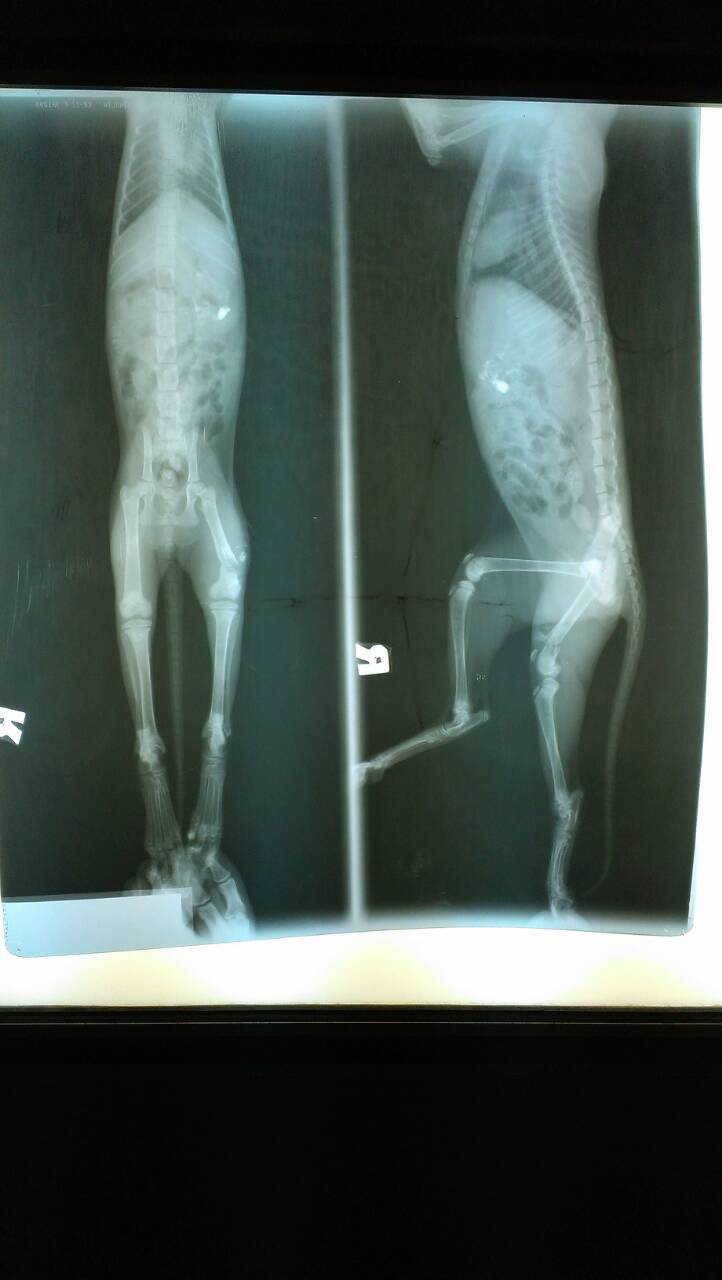

主題: 三個月小貓大腿粉碎性骨折癱軟在路中央險些被輾 申請者姓名: 康庭瑀 花色: 申請日期: 2013-11-27 18:07:58 申請者部落格: 申請者臉書網址: 所在縣市/合作醫院: 台南市/啄木鳥動物醫院 治療費用: 18950元 需求人數: 21人 已結案 (2014-01-10 17:50:13) 報名人員: Wendy x2(已付款)、Milkbau Lu(已付款)、vivian(已付款)、Jocelyne YuYu Kao(已付款)、臺北市支持流浪貓絕育計劃協會(代MD饅頭希望報名)(已付款)、蔡秀芳、小揚、王千枝 x2(已付款)、Cha-Mei Huang(已付款)、Bubu Wang(已付款)、林建華(已付款)、Wendy Tseng(已付款)、David Wei(已付款)、Crystal x4(已付款)、ERic YU(已付款)、林學凱(已付款)、chiawei x2(已付款)、 候補人員: 動物病情說明: 11/14下午約17:20左右,我要騎車去買東西,隱隱約約看到路中央有個白色東西,騎近一看,是隻小貓,車水馬龍,差點被車輾過!路上人車趕下班的趕下班,買東西的買東西,就是沒有人肯伸出援手拯救牠,就連把牠移到路邊也不肯。基於愛護流浪貓咪的精神,我馬上把他撈起來放在路邊,發現他不能走路,只能用爬的,且還有外傷,身體很臭,一身白毛染成灰黑色,且感覺很餓,不知道幾天沒吃東西了,又受傷又沒東西吃,貓是愛乾淨的動物,身體卻髒兮兮的,真的很可憐。於是我馬上送到附近的獸醫院,醫生說他大腿骨折了,但自家沒有儀器可檢查,需送至台南市區,於是我馬上帶小貓衝去市區先施打消炎針、照x光,發現一隻大腿粉碎性骨折,獸醫院說必須先住院觀察才能開刀,抽血檢查發現小貓肝指數很高,必須施以打針跟藥物治療,且白血球也很高,不排除傷口有感染的情況,還脫水,情況非常糟糕。於是當晚就住院了,由醫護人員悉心照料,第二、三次抽血檢查肝指數和白血球的情況有慢慢好轉了,但是脫水情況改善了,卻發現有貧血的問題,所以還另外驗了血型,開刀手術額外了輸血的步驟。開完刀後小貓就繼續住院,食慾體力恢復得很好,等拆完線就能出院了。 動物近況說明: 11/20開刀,用了骨釘,狀況良好,等拆線出院